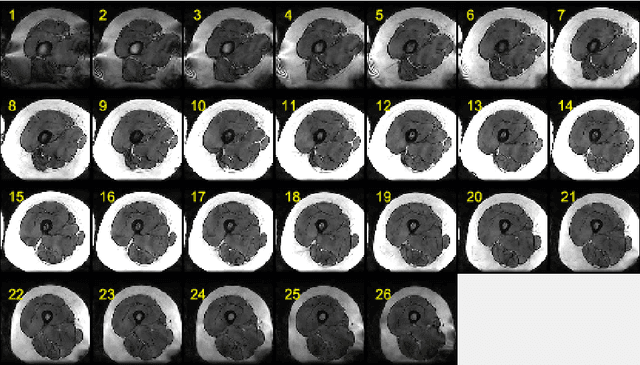

Abstract:This paper presents an end-to-end solution for MRI thigh quadriceps segmentation. This is the first attempt that deep learning methods are used for the MRI thigh segmentation task. We use the state-of-the-art Fully Convolutional Networks with transfer learning approach for the semantic segmentation of regions of interest in MRI thigh scans. To further improve the performance of the segmentation, we propose a post-processing technique using basic image processing methods. With our proposed method, we have established a new benchmark for MRI thigh quadriceps segmentation with mean Jaccard Similarity Index of 0.9502 and processing time of 0.117 second per image.